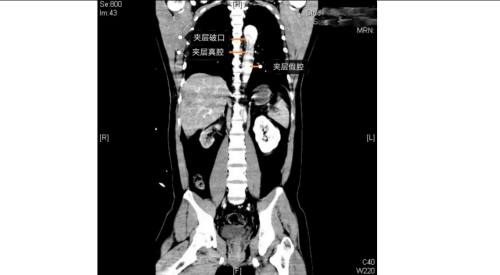

医院急诊科、麻醉手术科、外周血管介入科、急诊重症监护室等多学科团队火速响应。外周血管介入科主任、主任医师赵扬程及团队迅速评估患者病情并果断决定立即急诊手术。赵扬程指出,影像显示患者主动脉内膜严重撕裂,血流冲入血管壁形成巨大“假腔”。危急的是,夹层广泛累及腹腔主干血管,导致双下肢血管完全撕闭,下肢冰冷。此时主动脉壁薄如蝉翼,分秒间可致命破裂!同时,下肢及腹腔脏器严重缺血,如不迅速开通血管,将迅速引发肢体坏死、多器官衰竭。

手术室内,患者血压一度飙至惊人的320/150mmHg,循环濒临崩溃!麻醉团队全力稳定循环。在患者下肢几乎无法触摸到脉搏的极端条件下,外周血管介入科主任赵扬程及团队迎难而上,凭借精湛技术,精准置入支架,成功封堵主动脉内膜巨大破口,并精细重建了主动脉弓部受累的重要分支血管,恢复关键血流。这场持续近3小时的手术每一步都高风险且高度紧张,如同在死神面前进行“拆弹”。最终,这颗“血管炸弹”被成功拆除。